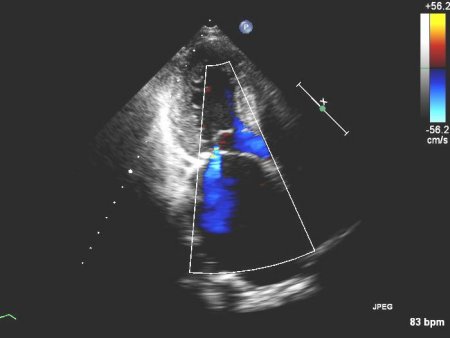

Regurgitação mitral

Corte apical de 4 câmaras de regurgitação mitral 1-2+ posterior

Do acervo de Samir Kapadia e Mehdi H. Shishehbor